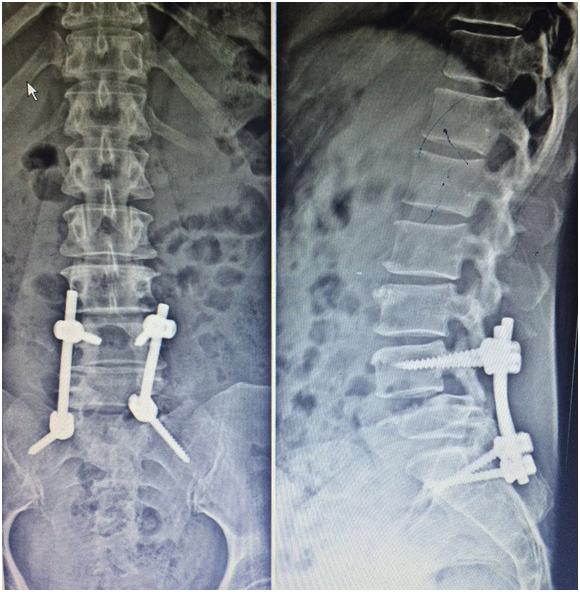

A 53 y.o female patient presented to the emergency of another hospital after she was involved in a motor vehicle accident and was diagnosed to have traumatic L4-5 spondylolisthesis (Figure 1). She was complaining of severe low back pain along with inability to mobilize her feet. Physical exam showed absence of motor power in both dorsiflexion and plantar flexion of both feet. There was also complete loss of sensation in all feet dermatomes. She was taken to the operating room immediately where laminectomy to decompress the neural elements was done along with repair of a massive dural tear. Several attempts to reduce the dislocation were unsuccessful and In-situ bone grafting with instrumentation between L4 and Sacrum was performed (Figure 2). Postoperatively, the right foot dorsiflexion improved to 2/5 for only 8 days and then became again 0/5 while the left foot did not show any sign of improvement. A brace was applied and the patient was stabilized and discharged home on physical therapy exercises for the following 3 months.

Figure 2 In-situ fusion with instrumentation between L4 and Sacrum was performed.